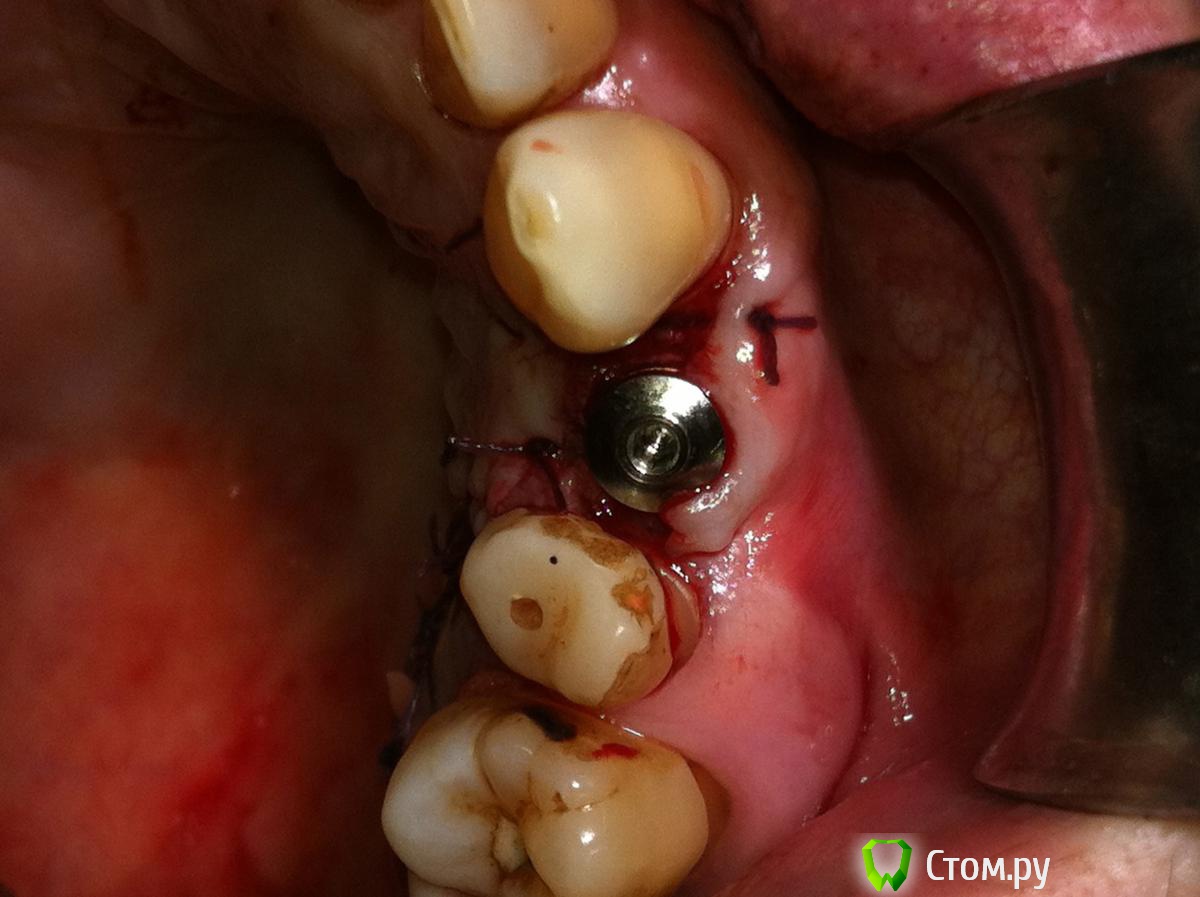

Tabula Rasa Опубликовано 29 сентября, 2014 Поделиться Опубликовано 29 сентября, 2014 (изменено) Пациент Л, 65 летИмплантация в области 2.4. Ожидание 4-4.5 месяца->недостаток мягких тканей и к тому же явный "завал" вестибулярного овала->ротированный лоскут на ножке одновременно фиксируемый формирователем->1 месяц->протезирование.Окончательным результатом не до конца доволен,т.к десна все равно усела и по высоте,и по ширине...думается ошибка в отсутствие временной коронки на импланте была. Изменено 29 сентября, 2014 пользователем IlyaPM Ссылка на комментарий

Alexey Doc Опубликовано 30 сентября, 2014 Поделиться Опубликовано 30 сентября, 2014 Мне тоже кажется что винт вестибулярно стоит Ссылка на комментарий

Дмитрий Никитюк Опубликовано 30 сентября, 2014 Поделиться Опубликовано 30 сентября, 2014 Мне тоже кажется что винт вестибулярно стоит Креститься нужно , а лучше штангенциркуль взять: http://s017.radikal.ru/i432/1409/a3/aa03dee0bb19.png Видно как топикстартер вышел за пределы эстетического окна. В таких условиях рассчитывать на суперрезультат не приходится. Но не смертельно. 9 Ссылка на комментарий